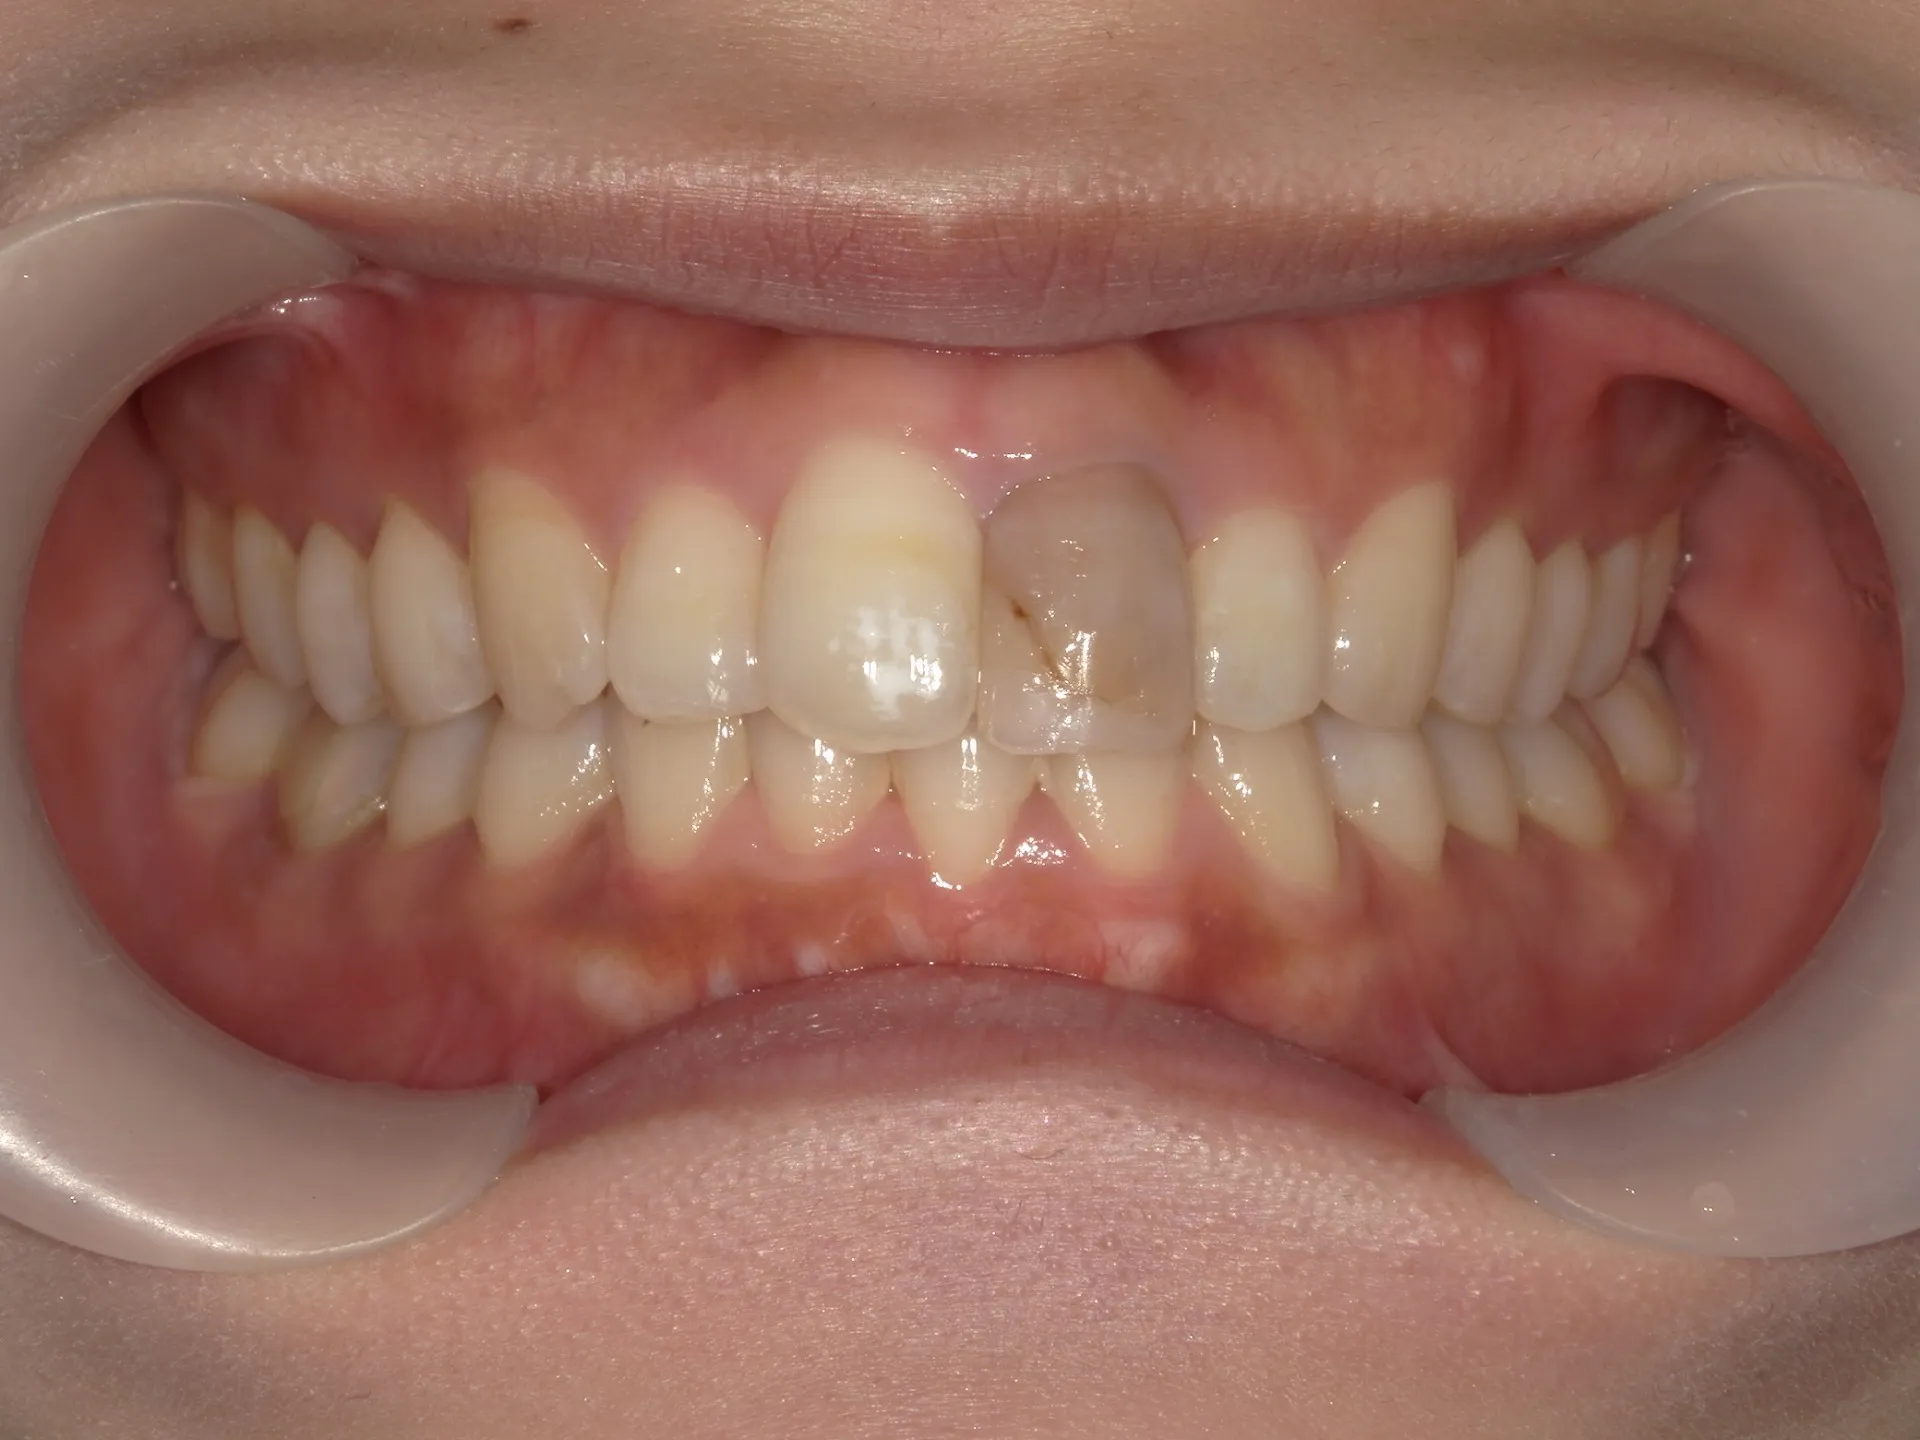

大きく飛び出してしまった前歯の矯正と変色の治療を希望された症例をご紹介いたします。